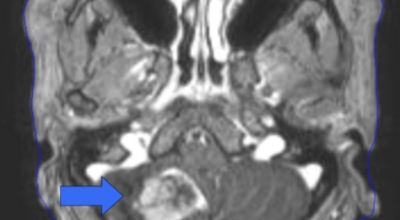

가장 흔한 뇌종양은 수막종이며 종양의 크기나 위치에 따라 수술이 필요하지 않을 수 있지만 청각 신경초종은 이명을 발생시킬 수 있다고 하며 심한 경우 안면 마비, 경련 및 통증을 발생시킬 수 있지만 뇌종양은 생존을 좌우하게되는 교모세포종 문제가 뒤늦게 생기는 것으로 주의가 필요한 이유이예요.

뇌종양이 악성인 경우, 빨리 자라는 특성이 있기 때문에 수술적으로 절제가 필요할 수 있습니다. 하지만 수술로 종양이 완벽하게 제거가 어려운 경우, 수술 후에 방사선 치료와 항암치료를 추가적으로 시행되어요. 요즘 들어서 뇌조직의 훼손을 최소화하고 수술 흉터가 거의 남지 않는 방법으로 하는 치료인 감마나이프 방사선 수술이 있답니다. 이 방사선 수술은 전신 마취와 피부 절개가 필요 없으며, 합병증이나 후유증이 적은 것으로 알려져 있답니다.